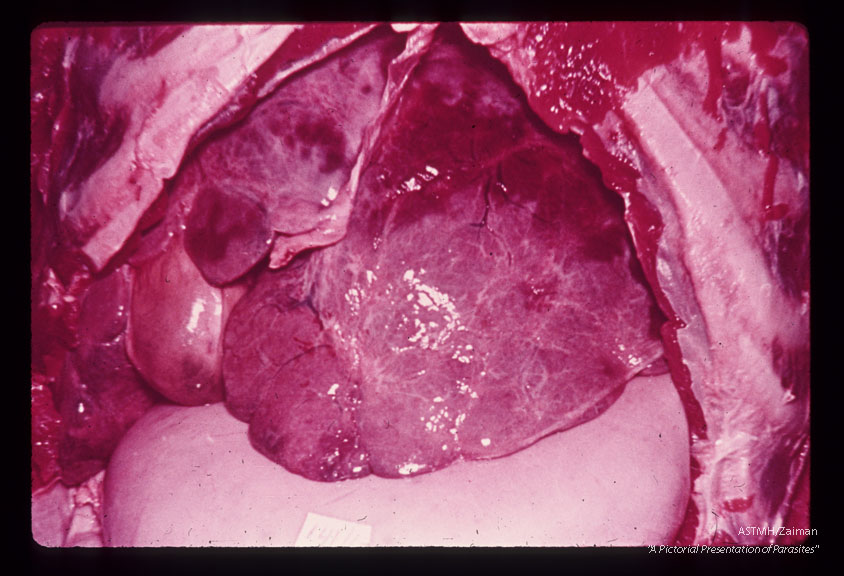

Autopsy specimen of 27 year old Brazilian male who died of hematemesis associated with hepatosplenomegaly. One hundred-eighty-three active adult pairs were counted at autopsy. The external surface of the liver was bosselated. Although this was the most typical appearance, the liver surface is sometimes smooth or finely nodular in such cases.

Schistosoma mansoni

Description: Autopsy specimen of 27 year old Brazilian male who died of hematemesis associated with hepatosplenomegaly. One hundred-eighty-three active adult pairs were counted at autopsy. The external surface of the liver was bosselated. Although this was the most typical appearance, the liver surface is sometimes smooth or finely nodular in such cases.